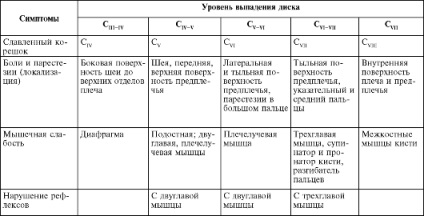

Adja meg a diagnózist az orvos a diagnózis után helyes. De ott volt egy porckorongsérv, megjelenik a következő tünetek (lásd. Az alábbi táblázatot).